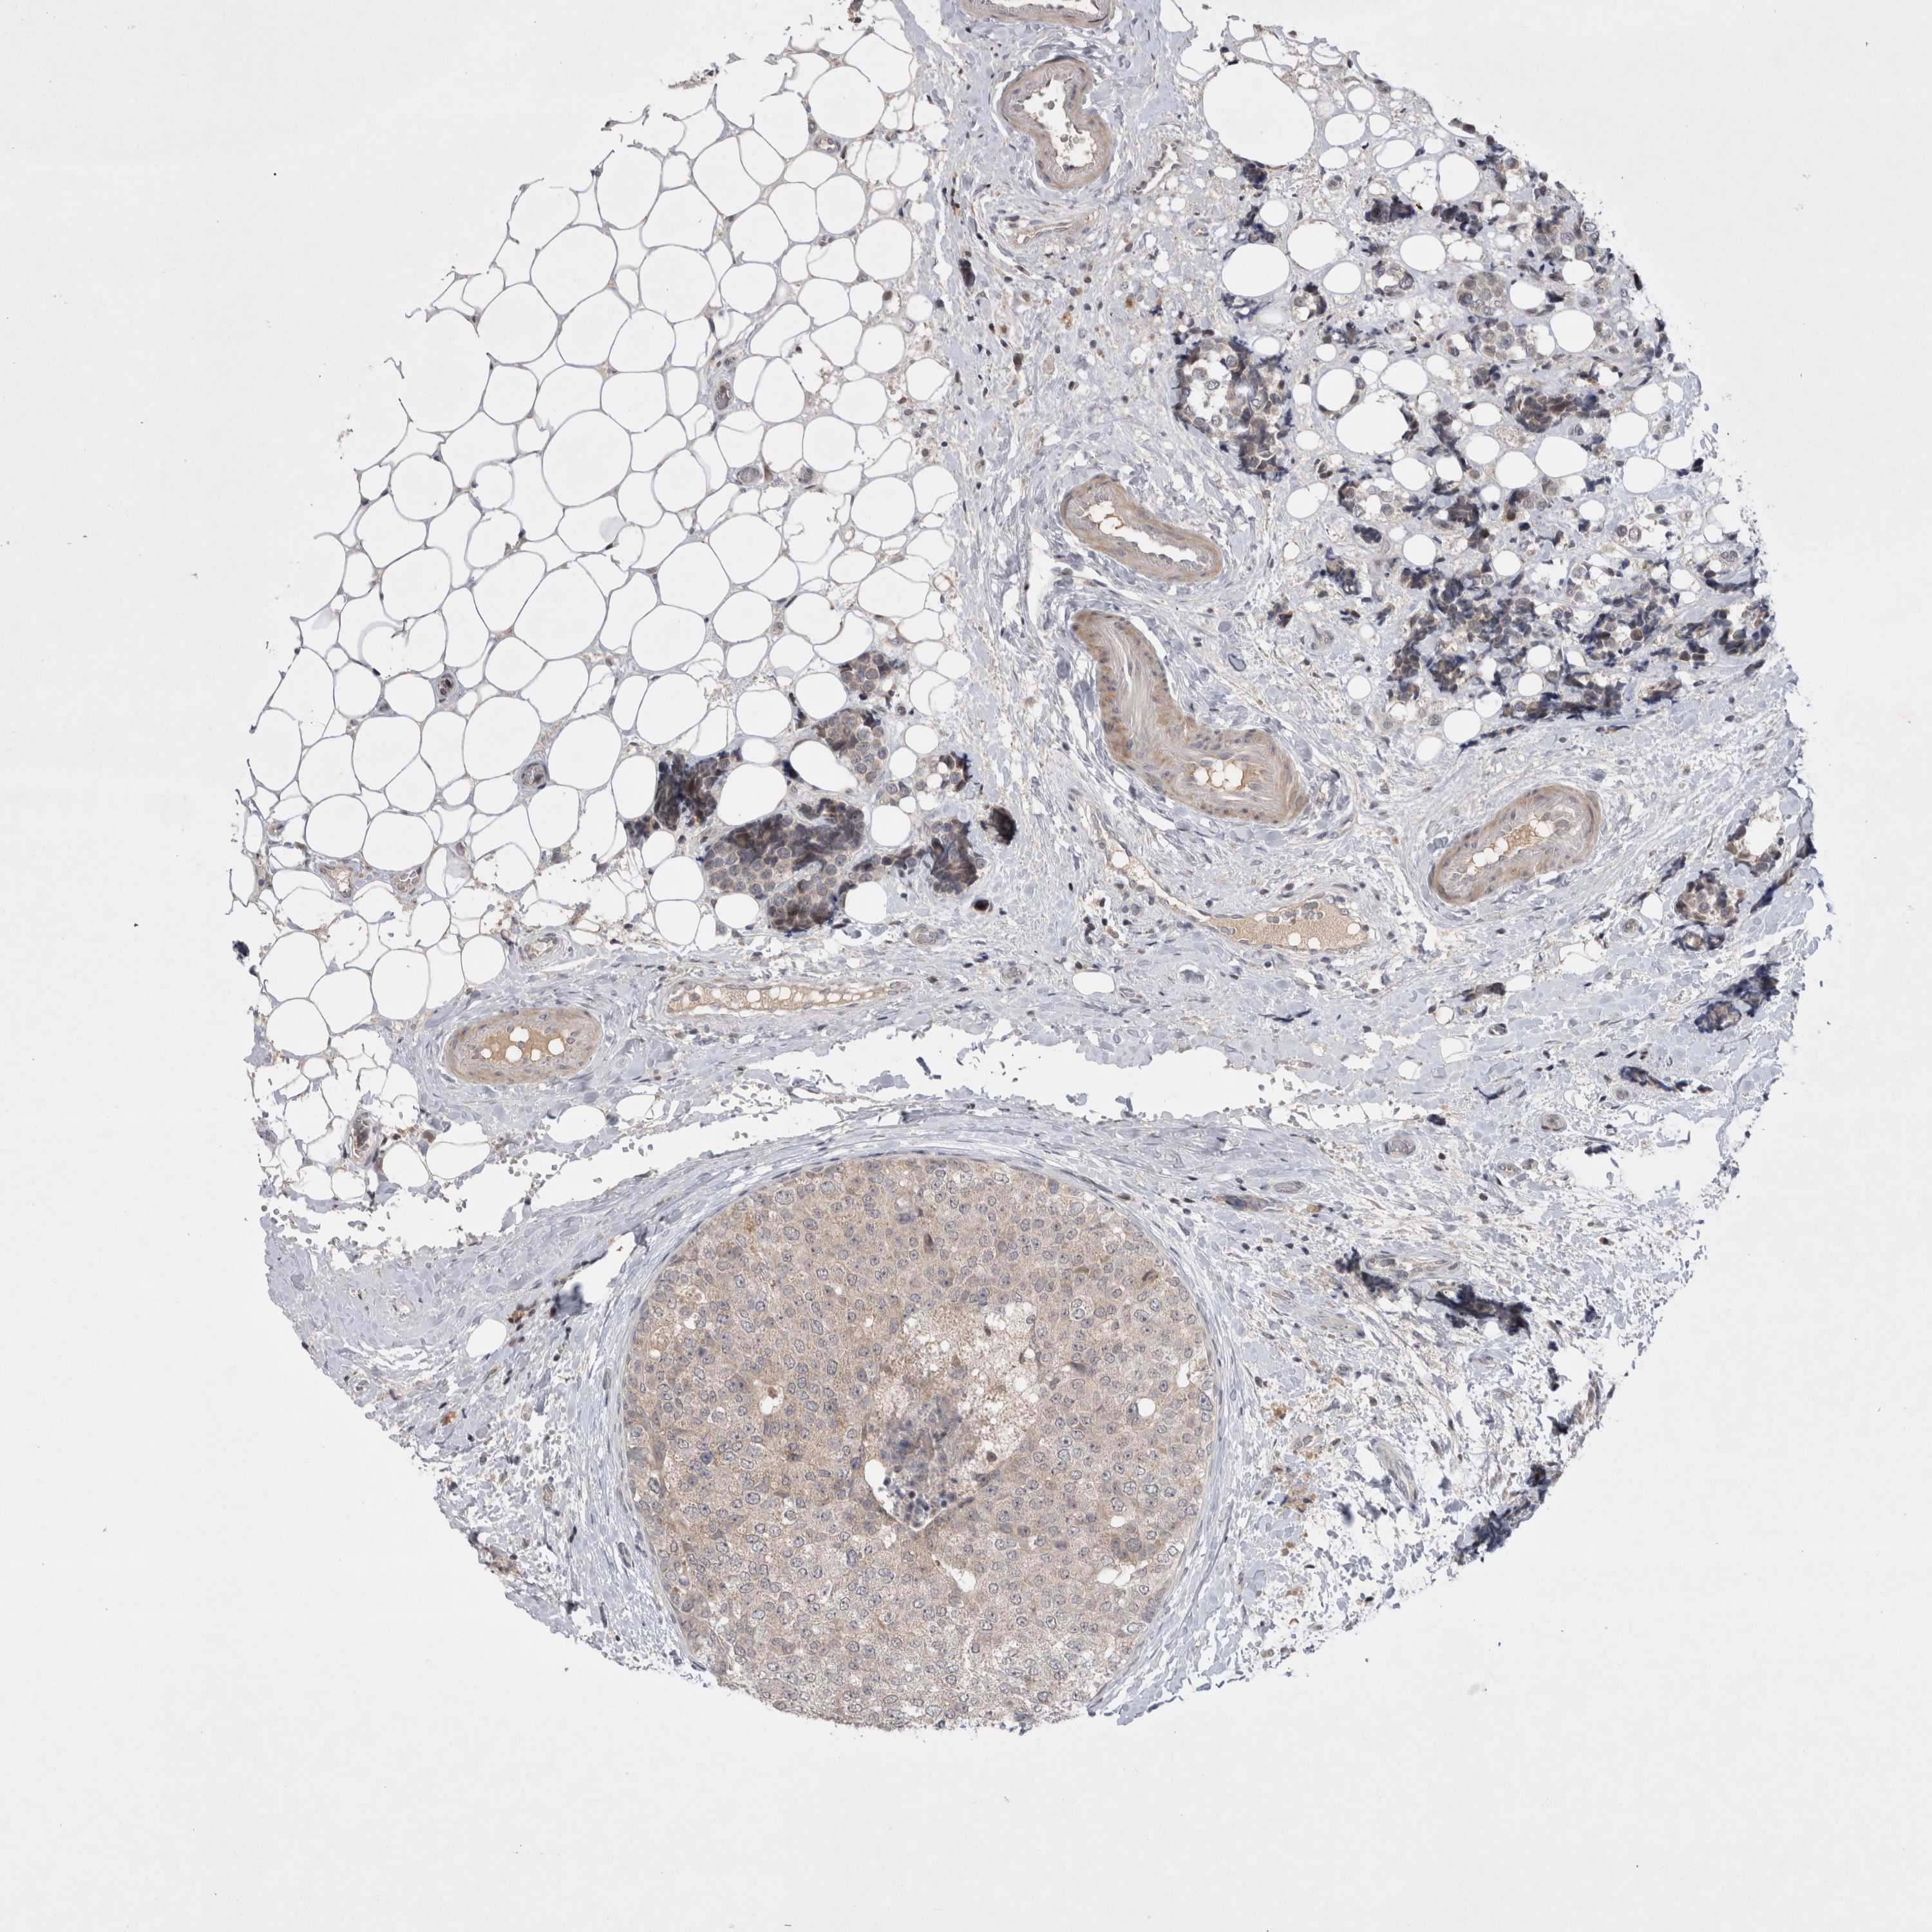

CANCER BREAST CANCER Show tissue menu

BRCA TCGA BRCA VALIDATION PROTEIN EXPRESSION

Breast cancer

Human cancer